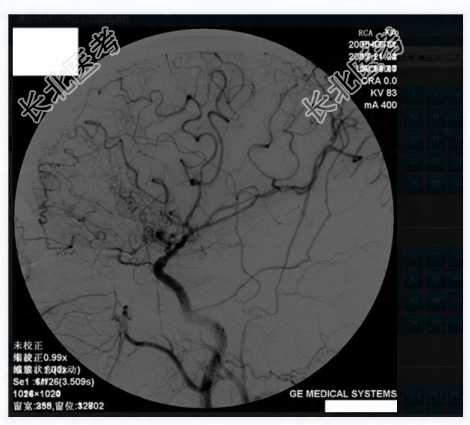

- 多项选择题3.提示:患者急诊行开颅探查、血肿清除、去骨瓣减压术, 术后一周后行全脑血管DSA,见下图。从上可能得出的诊断有

A、前交通动脉瘤

B、脑动静脉畸形

C、脑动脉粥样硬化性狭窄

D、硬脑膜动静脉瘘

E、烟雾病

F、海绵状血管畸形